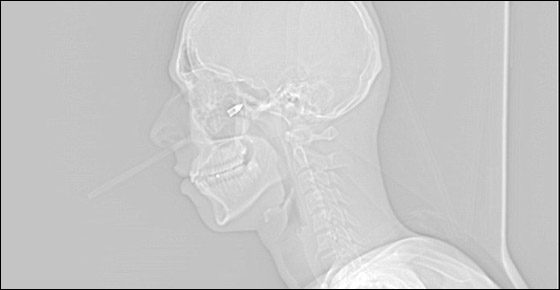

واظهرت صور الاشعة السينية (رينتغن)، كسرا في عظام خدّه الايمن، الا انه ولحسن الحظ نجا باعجوبة من تلف الاعصاب والشرايين في خده، حيث كانت تبتعد عن مكان الاصابة 2 مللمتر فقط. وحول الحادثة، قال لويس: "لم اشعر حقا بدخول السهم في خدّي الايمن، فقد دخل بسرعة فائقة وبقوة، وسألت صديقي، هل دخل السهم في خدّي؟! فلم اكن اشعر بألم في البداية، ولم اصدق ما حصل، كان ذلك غير واقعي".